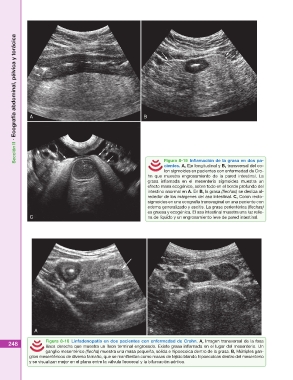

Figura 8-15 Inflamación de la grasa en dos pa-

cientes. A, Eje longitudinal y B, transversal del co-

lon sigmoides en pacientes con enfermedad de Cro-

hn que muestra engrosamiento de la pared intestinal. La

grasa inflamada en el mesenterio sigmoides muestra un

efecto masa ecogénico, sobre todo en el borde profundo del

intestino anormal en A. En B, la grasa (flechas) se desliza al-

rededor de los márgenes del asa intestinal. C, Colon recto-

sigmoides en una ecografía transvaginal en una paciente con

edema generalizado y ascitis. La grasa perientérica (flechas)

es gruesa y ecogénica. El asa intestinal muestra una luz relle-

C na de líquido y un engrosamiento leve de pared intestinal.

Figura 8-16 Linfadenopatía en dos pacientes con enfermedad de Crohn. A, Imagen transversal de la fosa

iliaca derecha que muestra un íleon terminal engrosado. Existe grasa inflamada en el lugar del mesenterio. Un

ganglio mesentérico (flecha) muestra una masa pequeña, sólida e hipoecoica dentro de la grasa. B, Múltiples gan-

glios mesentéricos de diverso tamaño, que se manifiestan como masas de tejido blando hipoecoicas dentro del mesenterio

y se visualizan mejor en el plano entre la válvula íleocecal y la bifurcación aórtica.